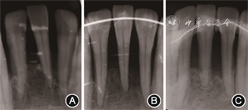

(2)临床及影像学检查:全口口腔卫生差,软垢指数为3,牙石(+++);全口牙龈充血红肿,质地松软,局部位点自发性出血;全口探诊出血(bleeding on probing,BOP)阳性位点百分比为100%(156/156),全口探诊深度(probing depth,PD)2~14 mm,其中PD≥5 mm的位点占64.1%(100/156),临床附着丧失(clinical attachment loss,CAL)2~14 mm;17、31、36、37、41、44、47Ⅲ度松动,多颗牙Ⅰ~Ⅱ度松动;17、36根分叉病变Ⅲ度,16根分叉病变Ⅱ度,26、27、37、47根分叉病变Ⅰ度(图1)。全口曲面体层X线片示全口牙槽骨吸收至根长的1/2至2/3,17、36、31、41、44牙槽骨吸收近根尖(图2)。14、35缺失,44、28伸长;上前牙扇形移位,11与21间隙约4 mm,前牙Ⅲ度深覆

、Ⅱ度深覆盖,双侧磨牙中性关系(图3)。

(1)牙周基础治疗:2017年6至11月,拔除预后无望患牙17、36、41、44和3颗第三磨牙18、28、48,完成龈上洁治、龈下刮治及根面平整术,使用复方氯己定含漱液(口泰,深圳南粤药业有限公司)含漱(20 ml/次,2次/d,10 d),并口服奥硝唑(固特,湖南九典制药股份有限公司)分散片(500 mg/次,2次/d,5 d)。复查显示口腔卫生良好,牙龈色粉红,质地坚韧(图4)。由于上前牙仍然存在PD>5 mm的位点,且根尖X线片显示11、21间牙槽骨呈垂直型吸收,建议行牙周再生性手术。